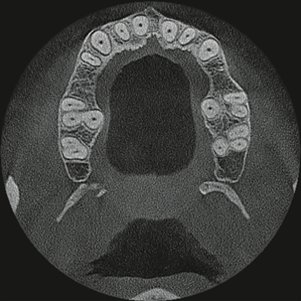

3D Cone Beam CT (100×100mm)

歯根状態を分析できる100μmの高画質画像を取得し、下歯槽管と上顎洞の構造分析に最適なCBCTです。

撮影から画像構成まで33秒であるため、インプラント手術中にも、位置や手術の方向性を迅速に確認出来ます。